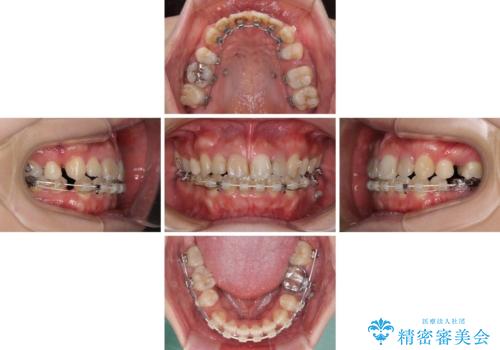

- 矯正装置

- ハーフリンガル

抜歯矯正が必要であることはご自身で理解されており、目立たない装置をご希望であったので、上顎が裏側装置であるハーフリンガル装置にて治療を行うこととしました。

開咬の改善には舌突出癖を改善するためのトレーニングが必要ですが、しっかりと行っていただき、想定よりも早い期間で治療を終えることができました。